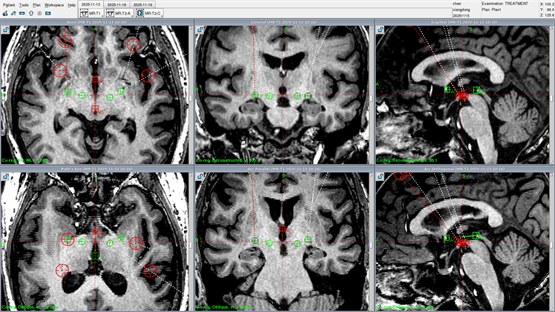

▲术前双侧SNr+GPi 四靶点手术规划

“这要求我们在术前影像规划时,就必须像工程师一样精确计算,确保四根电极在有限的颅内置入空间内‘各行其道’,互不干扰,最终精准抵达三个不同的功能核团。”郭主任补充道,“这对整个团队的经验、技术和默契都是极大的考验。”